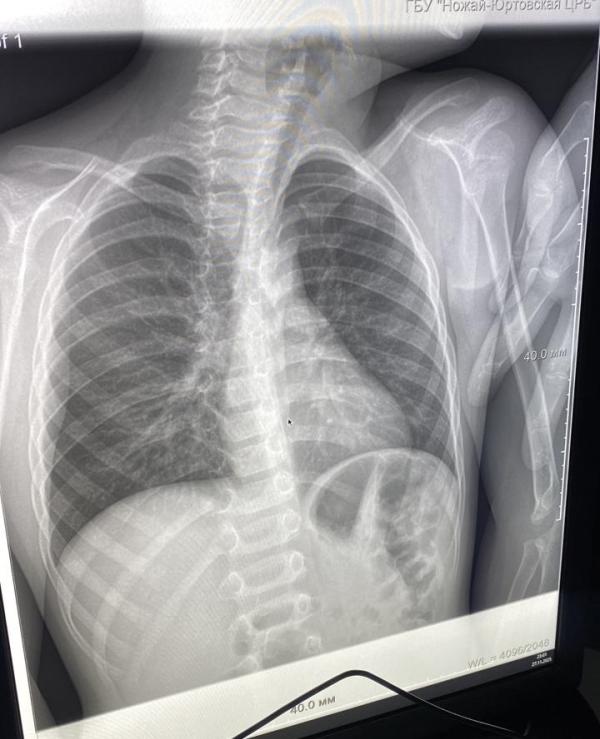

Д/з. Прикорневая пневмония справа

Это то ладно, вылечится, но вот сколиоз какой для такого возраста! И тень сердца сильно увеличена.